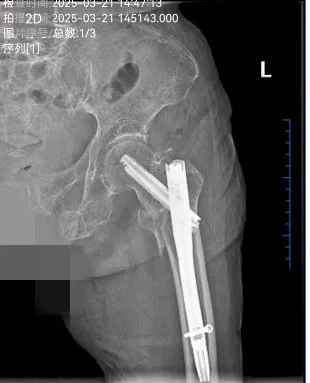

2025年3月,武寧(níng)縣總(zǒng)醫院人民醫院院區骨科團隊(duì)以精湛的技術和多學科協作模式,為一名(míng)104歲超高齡股骨粗隆間骨折(shé)患者成功實施微創(chuàng) Intertan 內固定術。這一壯舉不僅挽(wǎn)救了患者的生(shēng)命,更標誌著醫院在老年骨(gǔ)創傷救治領域取得了新的突破。

患者陳奶奶,今年104歲,因不慎跌倒導致左(zuǒ)側股骨粗隆間粉碎(suì)性骨折。她既往(wǎng)患有重度骨質疏鬆、低蛋白血症、心房(fáng)顫動、心功能不全、慢性阻塞性肺病(COPD)、脊柱畸形等多項基礎疾(jí)病。髖部(bù)骨折被稱為“人(rén)生最後(hòu)一次骨折”,保守治療會導致患者(zhě)長期臥(wò)床,不僅承受劇烈疼痛,還容易引發深靜脈血栓、肺部感染、褥瘡等嚴重並發症,死亡(wáng)率極高。

骨科團隊憑借豐(fēng)富的臨床經驗和先進的技術手(shǒu)段,采用國際領先的Intertan髓內釘係統,通過微創小切口完成複位固定。該係統具有雙螺釘設計,形成(chéng)更強的抗旋轉能力,提供更高的穩定性;同時利用滑動(dòng)加(jiā)壓(yā)原理,促進骨痂形成,顯著減少術後並發症的發生。手術(shù)僅曆時30分鍾,術中出血不到50毫升,極(jí)大地降低了(le)手術風險。